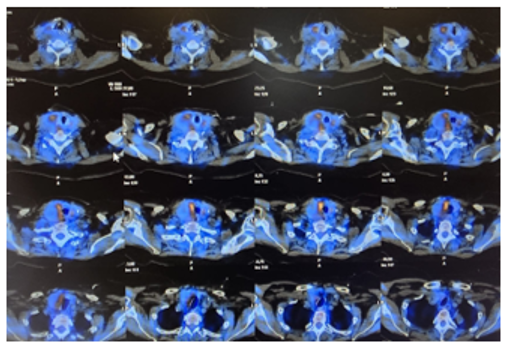

Parathyroid scintigraphy with SPECT/CT (Figure 1): Hypodense nodular image measuring 48 x 40 x 37 mm located in the LD, without MIBI or pertechnetate uptake.

A PET scan with methionine was requested: hypodense nodule in the thyroid logia with close contact with the right lobe and hyperuptake in the periphery, measuring 34 x 35 mm.